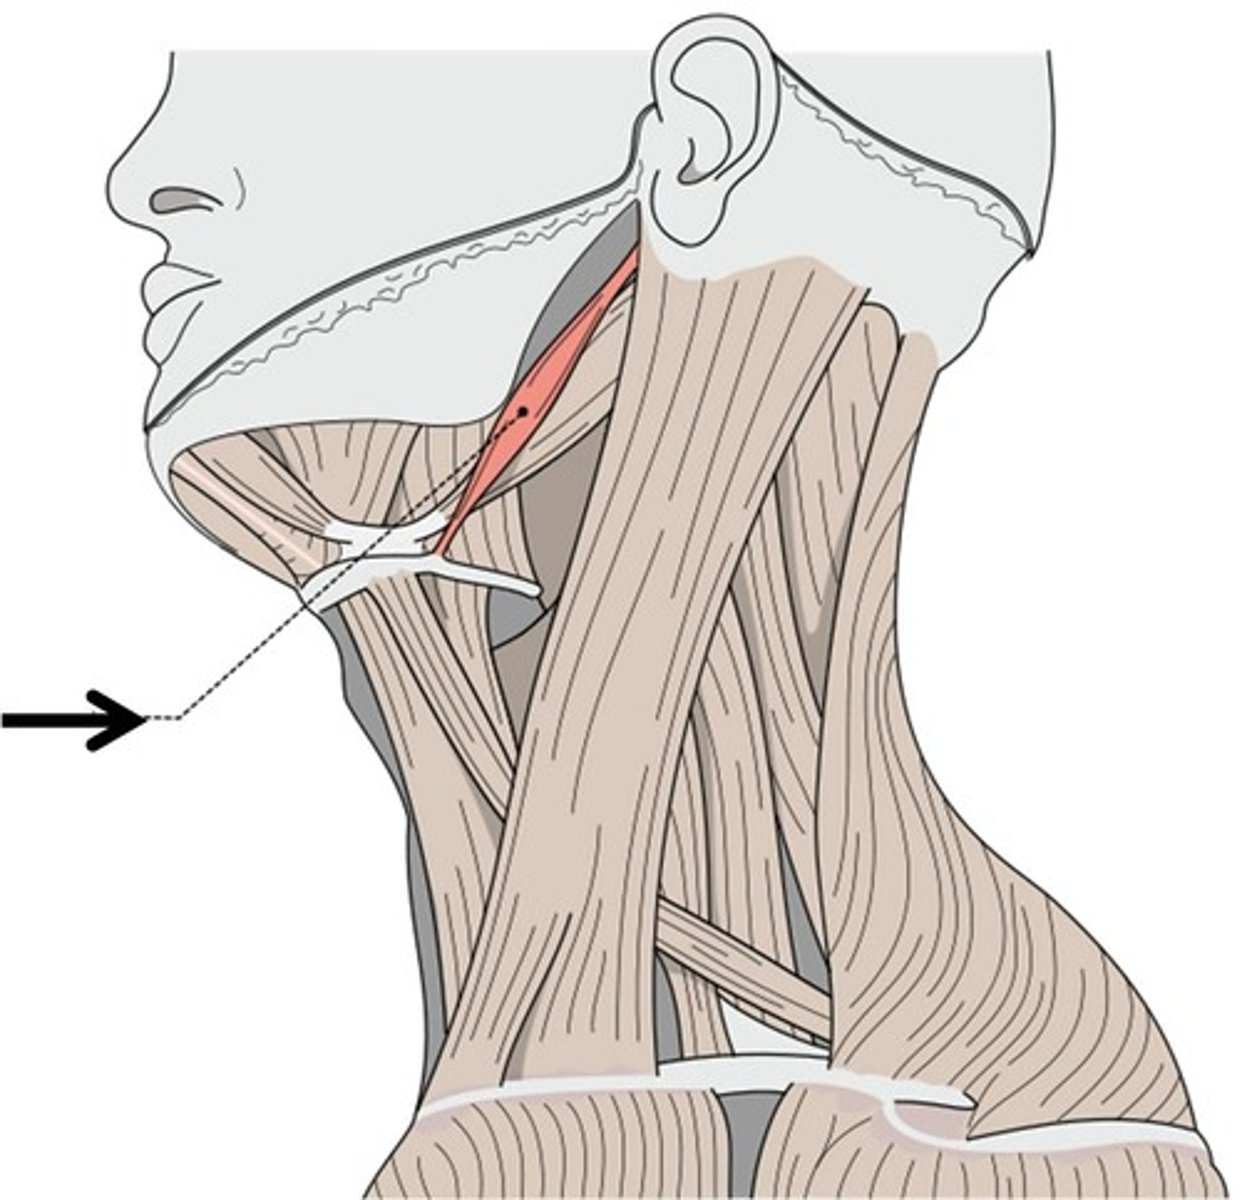

Sternocleidomastoid m.

Origin: Sternum/Clavicle

Insertion: Mastoid Process

Action: Flex, Rotate